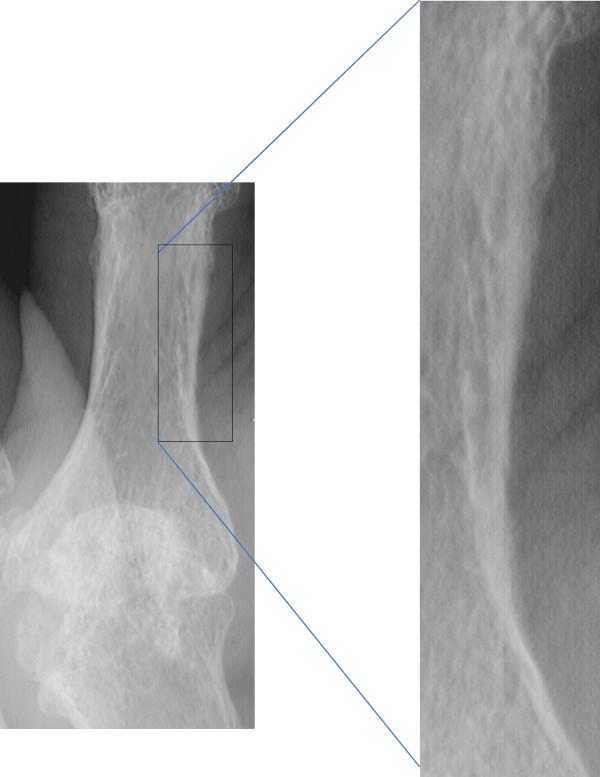

The concept of osteoimmunology is based on growing insight into the links between the immune system and bone at the anatomical, vascular, cellular, and molecular levels. In both rheumatoid arthritis (RA) and ankylosing spondylitis (AS), bone is a target of inflammation. Activated immune cells at sites of inflammation produce a wide spectrum of cytokines in favor of increased bone resorption in RA and AS, resulting in bone erosions, osteitis, and peri-inflammatory and systemic bone loss. Peri-inflammatory bone formation is impaired in RA, resulting in non-healing of erosions, and this allows a local vicious circle of inflammation between synovitis, osteitis, and local bone loss. In contrast, peri-inflammatory bone formation is increased in AS, resulting in healing of erosions, ossifying enthesitis, and potential ankylosis of sacroiliac joints and intervertebral connections, and this changes the biomechanical competence of the spine. These changes in bone remodeling and structure contribute to the increased risk of vertebral fractures (in RA and AS) and non-vertebral fractures (in RA), and this risk is related to severity of disease and is independent of and superimposed on background fracture risk. Identifying patients who have RA and AS and are at high fracture risk and considering fracture prevention are, therefore, advocated in guidelines. Local peri-inflammatory bone loss and osteitis occur early and precede and predict erosive bone destruction in RA and AS and syndesmophytes in AS, which can occur despite clinically detectable inflammation (the so-called 'disconnection'). With the availability of new techniques to evaluate peri-inflammatory bone loss, osteitis, and erosions, peri-inflammatory bone changes are an exciting field for further research in the context of osteoimmunology.

骨免疫学的概念基于对免疫系统和骨骼在解剖学、血管、细胞和分子水平上的联系的深入了解。在类风湿关节炎(RA)和强直性脊柱炎(AS)中,骨骼都是炎症的靶点。炎症部位的活化免疫细胞产生广泛的细胞因子,有利于 RA 和 AS 中骨吸收的增加,导致骨侵蚀、骨炎和炎症周围及全身性骨丢失。RA 中的炎症周围骨形成受损,导致侵蚀无法愈合,从而允许滑膜炎、骨炎和局部骨丢失之间形成局部恶性循环。相比之下,AS 中的炎症周围骨形成增加,导致侵蚀愈合、骨化附着点炎和骶髂关节和椎间连接潜在强直,并改变脊柱的生物力学能力。这些骨重塑和结构的变化导致椎体骨折(在 RA 和 AS 中)和非椎体骨折(在 RA 中)的风险增加,并且这种风险与疾病的严重程度有关,并且独立于和叠加于背景骨折风险。因此,指南提倡识别患有 RA 和 AS 且骨折风险高的患者,并考虑预防骨折。局部炎症周围骨丢失和骨炎发生较早,并且在 RA 和 AS 中的侵蚀性骨破坏和 AS 中的骨桥之前发生,并预测其发生,尽管临床上可检测到炎症(所谓的“脱钩”)。随着评估炎症周围骨丢失、骨炎和侵蚀的新技术的出现,炎症周围骨变化是骨免疫学领域进一步研究的一个令人兴奋的领域。